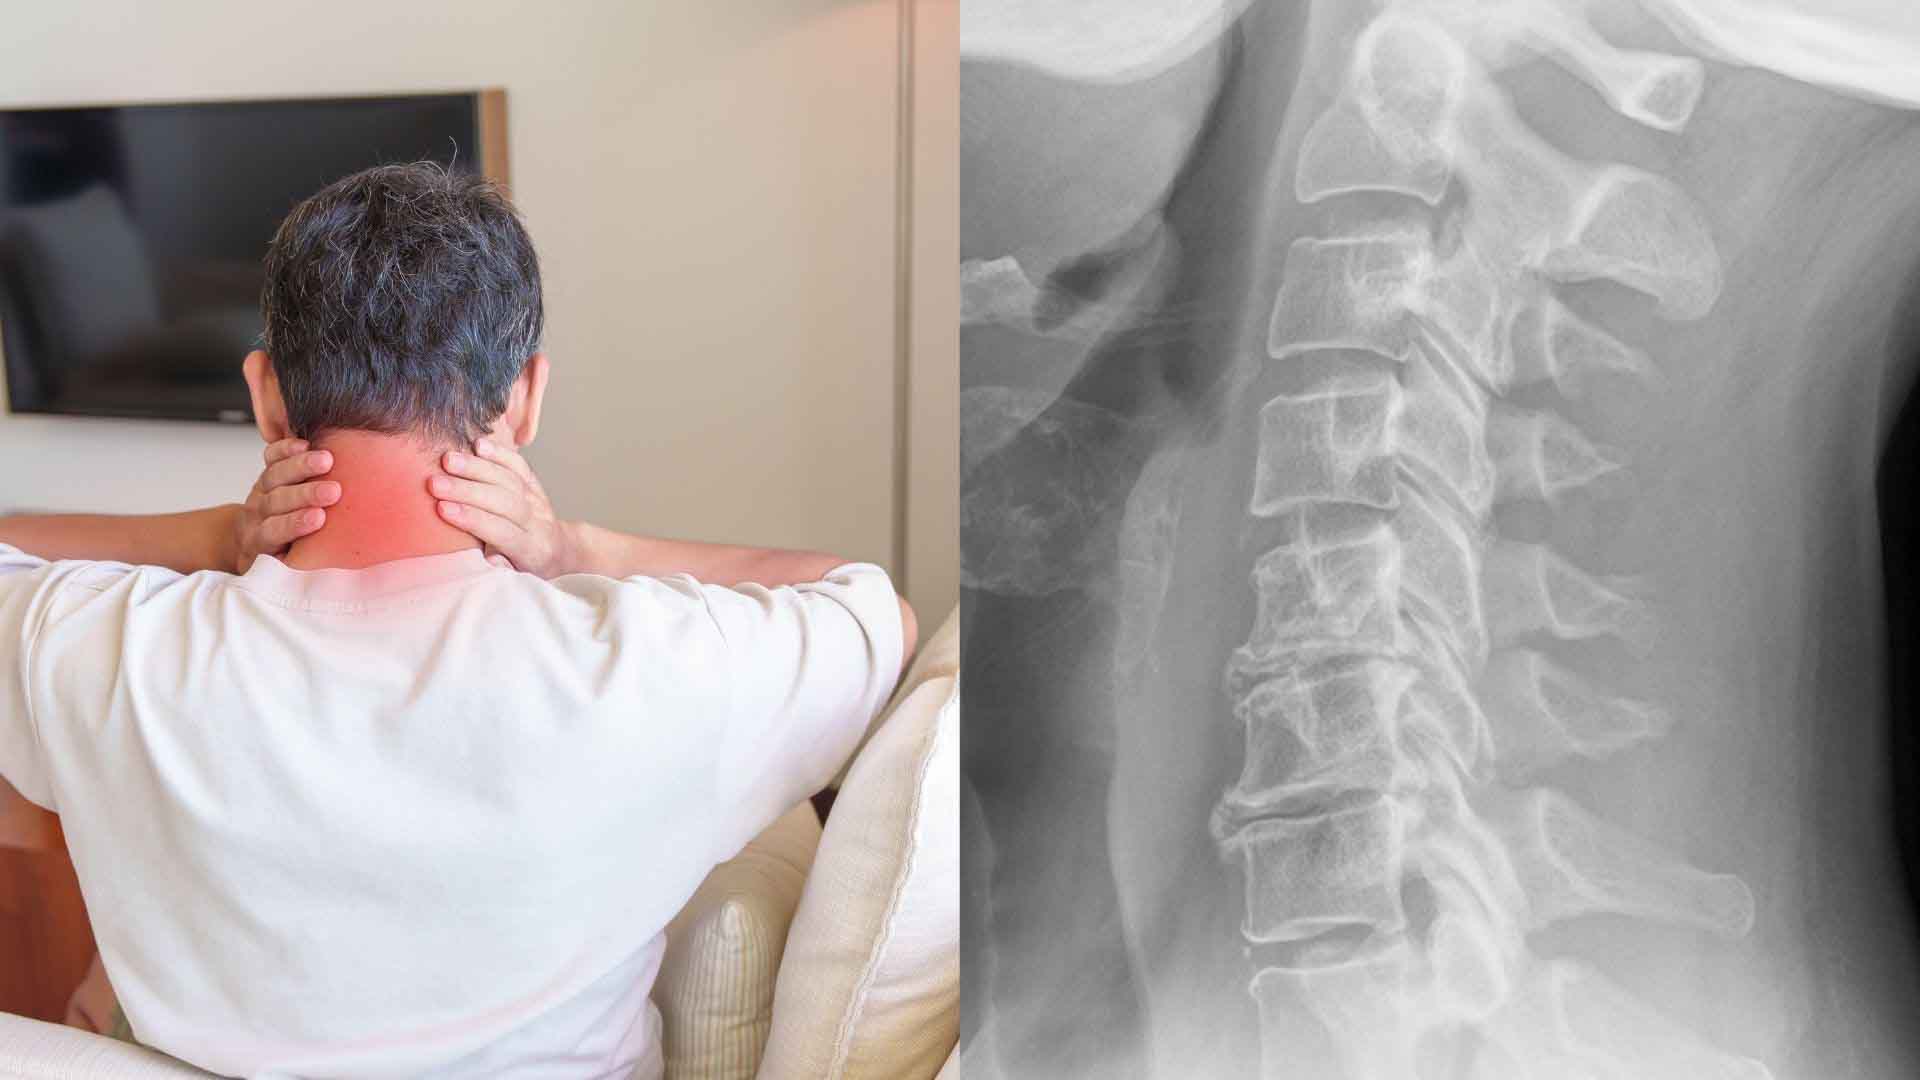

Các nguyên nhân gây thoái hóa đốt sống cổ

Các nguyên nhân gây thoái hóa đốt sống cổ. Đồ hoạ: Đinh Đinh